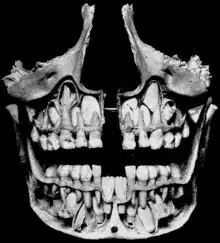

الأسنان اللبنية أو أسنان الحليب أو الرواضع[1][2] (أو الأسنان المتساقطة، أو أسنان الطفل، أو الأسنان المؤقتة، أو الأسنان الأولية [3]) وهي المجموعة الأولى من الأسنان في النمو التطوري للإنسان أو الثدييات ثنائية التسنين. تظهر هذه المجموعه خلال المراحل الجنينيه من التطور، وتبرز تصبح مرئيه في الفم خلال مراحل الطفولة. تفقد عادةً الأسنان اللبنية وتستبدل بالأسنان الدائمة، ولكن في غياب الإستبدالات الدائمه فإنها تستطيع البقاء نشطه وفعاله لعدة سنوات.

وهي أسنان[؟] بيضاء صغيرة الحجم ذات جذور قصيرة وتظهر من الشهر السادس، وقد يترافق ظهورها مع شيء من الألم، وغالبا ما تكون القاطعتان المركزيتان السفليتان هما أول سنين بازغتين، وتتوالى مجموعات الأسنان اللبنية بالبزوع حتى تكتمل في الفم في حوالي العامين والنصف.

يمتلك الطفل ما مجموعه عشرون سنا لبنية بحيث يحتوي كل فك على عشرة أسنان هي أربعة قواطع ونابان وأربعة طواحن مؤقتة. فيكون مجموعها 8 قواطع و4 أنياب و8 طواحن.

تستمر هذه الأسنان بالتشكل إلى أن تبزغ في الفم. في التسنين الأولي هناك ما مجموعه عشرون سن، خمسة لكل ربع وعشر اسنان لكل قوس سني. بزوغ هذه الأسنان يبدأ في عمر الست أشهر ويستمر حتى عمر 25-33 شهر خلال فترة التسنين الأولي.عادةً أول الأسنان الأوليه ظهوراً في الفم هي القواطع المركزي هالسفليه وآخرها ظهوراً الأرحاء الثانية العلويه. المجموعه السنيه الأوليه مكونه من: القواطع المركزية، القواطع الرباعيه، الأنياب، الأرحاء الأولى، الأرحاء الثانية؛ هناك واحد لكل ربع أي ما مجموعة أربع أسنان لكل نوع. كلها تُستبدل تدريجياً بأسنان دائمه مقابلة لها بإستثناء الأرحاء الأولى والثانية حيث تُستبدل بالضواحك. تحدد هذه الأسنان في "نظام تعيين الأسنان العالمي" بالأحرف الإنجليزية الكبيرهA-T.[3] استبدال الأسنان الأوليه يبدأ في سن السادسة عندما تبدأ الأسنان الدائمة في الظهور في الفم منتجةً ما يُعرف بالمجموعة السنية المختلطة. الأسنان الدائمة البازغة تسبب "ارتشاف الجذر، حيث تدفع الأسنان الدائمة جذور الأسنان الأولية مسببةً ذوبانها بوساطة خلايا آكله للسن، (بالإضافة لذوبان العظم السنخي المحيط بوساطة خلايا آكله للعظم). ثم تمتص بواسطة الأسنان الدائمة المتكونة. عملية تساقط الأسنان الأولية واستبدالها بالأسنان الدائمة تدعى"التقشير"، وقد تستمر هذه العملية من عمر الست سنوات إلى اثني عشرة سنة وعادةً في عمر الإثني عشر تبقى الأسنان الدائمة فقط.